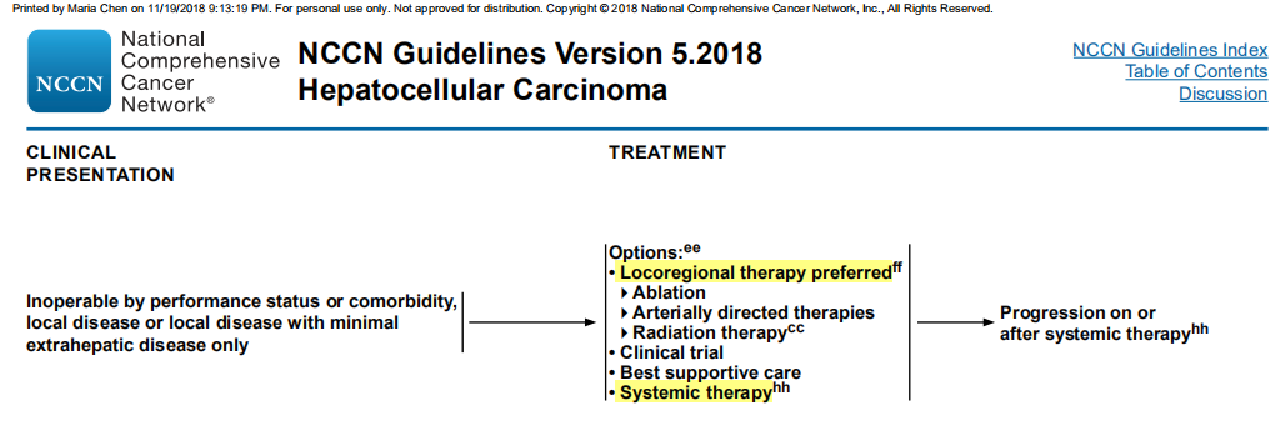

NCCN指南的治疗方案: